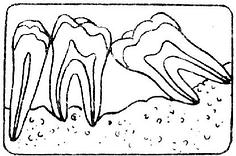

牙周袋形成:由于炎症的扩展,牙周膜被破坏,牙槽骨逐渐吸收,牙龈与牙根分离,使龈沟加深而形成牙周袋。可用探针测牙周袋深度。X线检查时可发现牙槽骨有不同程度的吸收。如图3-7~11.

| 图3-7 正常牙槽骨 | 图3-8 牙槽骨Ⅰ度吸收 |